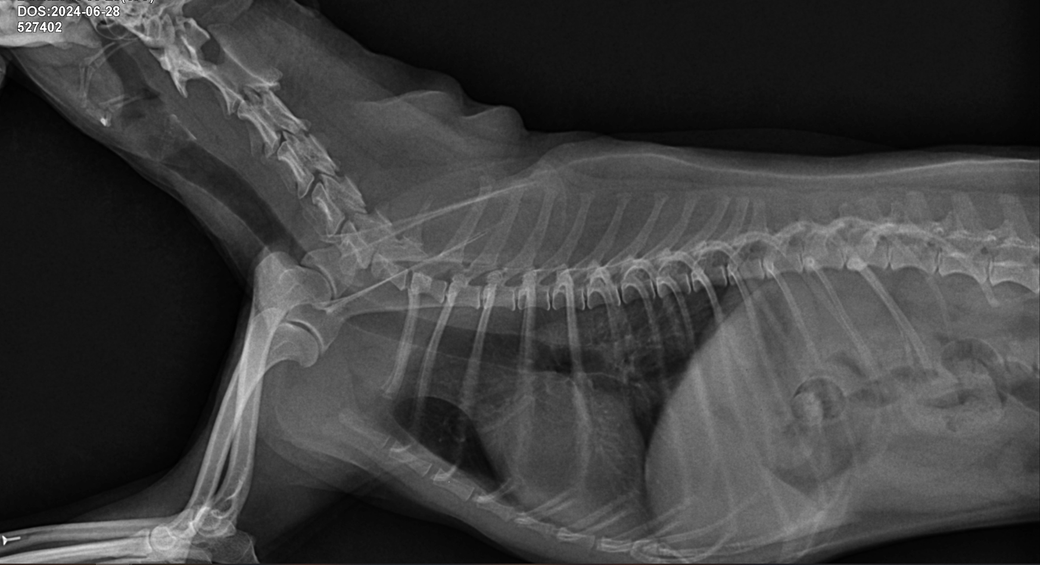

(6월 말입니다 사진 우측 화살표 클릭시 사진 커집니다)

공격적인 치료가 필요한 수준의 이상 상태는 아닌것으로 판단되니 환자를 직접 본 주치의의 판단을 따르시기 바랍니다. 또한 아래 사진처럼 경추 디스크 가능성이 있으니 이 부분에 대해서도 상담 받으시기 바랍니다.